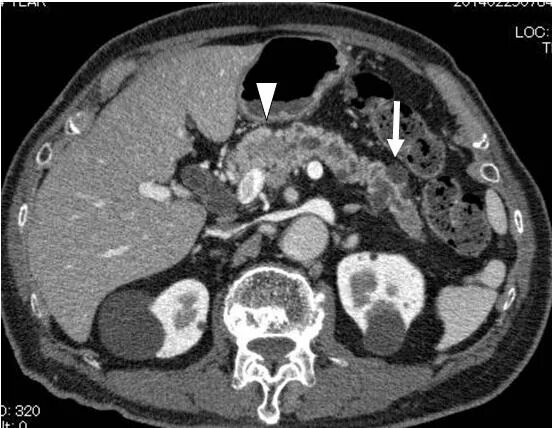

Диффузные изменения поджелудочной железы по типу стеатоза